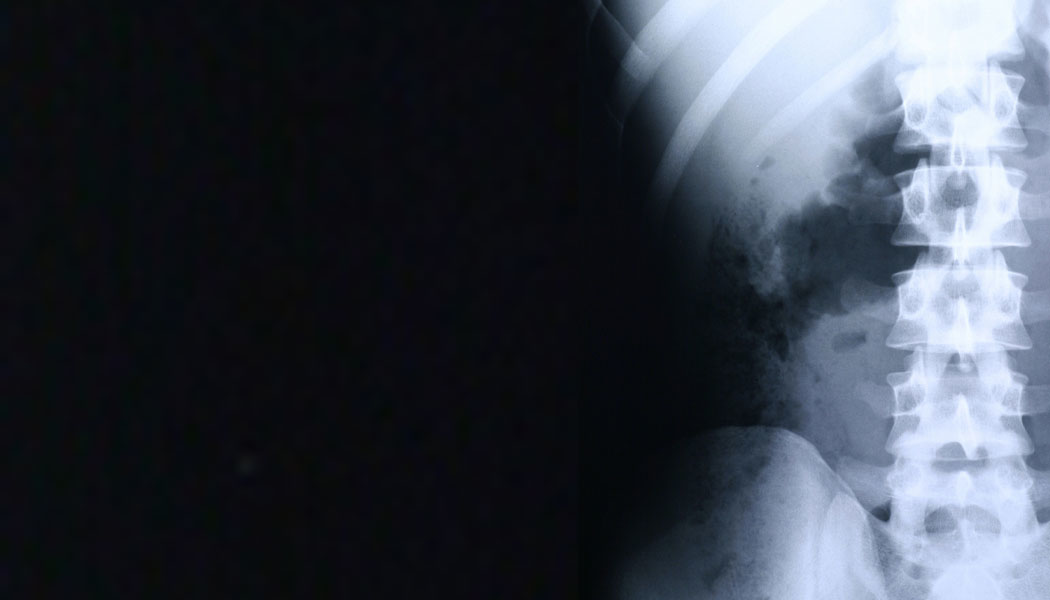

One major source of injury to healthcare workers is musculoskeletal disorders (MSDs). In 2017, nursing assistants had the second highest number of cases of MSDs.

Direct and indirect costs associated with only back injuries in the healthcare industry are estimated to be $20 billion annually.2